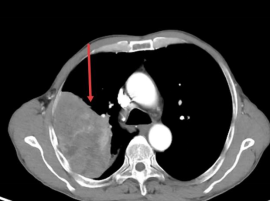

2024年12月,李大爷因持续“咳嗽、咳痰”就诊,经检查确诊为右肺腺癌,且病情已进展至IIIB期(cT4N2M0)(肺癌的临床分期,IIIB期属于中晚期,治疗难度较大)。当时,李大爷肺部肿瘤直径达11.5cm×7cm,同时伴随纵隔及肺门淋巴结肿大,不适合开展手术,治疗陷入僵局。

经过2周期的精准化疗,2025年8月26日,李大爷复查CT结果显示肺部肿瘤已缩小至4.3cm×2.3cm,疗效评估达到部分缓解(PR)。这一显著的“降期”效果,为李大爷赢得了宝贵的手术机会。“这个结果令人振奋。”主管医师严双丽表示,“通过我们精准的化疗方案,不仅有效控制了肿瘤进展,更重要的是实现了临床降期,为患者创造了根治性手术的条件。这充分体现了肿瘤内科在转化治疗中的关键作用。”

2025-2-25,肺部肿瘤巨大